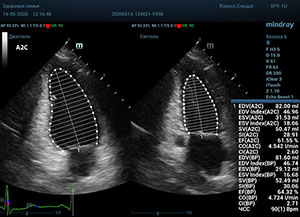

Что могут предложить современные приборы? Приборы нашего времени являются мощными вычислительными машинами, способными обрабатывать полученную информацию даже без помощи человека. Система автоматического вычисления фракции выброса – AUTO EF на приборах серии Resona компании Mindray сделает все за вас. За пару секунд прибор сам отыщет нужную фазу сердечного цикла и произведёт измерение и расчеты, а также покажет график изменения объема в сердечном цикле. От Вас требуется только получить качественное 4С и 2С сечение. Впрочем, прибор всегда оставляет возможность коррекции, если доктор имеет свое мнение на расположение точек планиметрии или момента измерения по ЭКГ каналу.